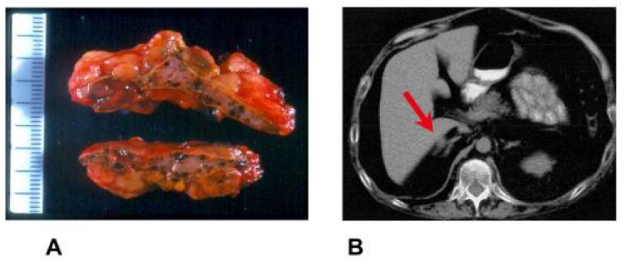

Figure 6. Macroscopic and CT-scan findings in primary pigmented nodular adrenocortical disease (PPNAD). A: Macroscopic appearance of the adrenal gland where multiple pigmented micronodules are evident at the cut surface. B: Adrenal CT scan revealed a micronodule on the external limb of the left adrenal (see red arrow). Copyright © 2006 Bertherat; licensee BioMed Central Ltd.